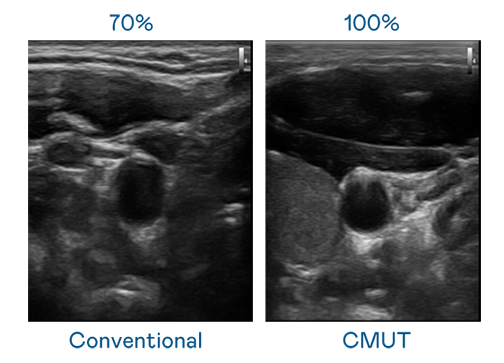

CMUT 技术是一种用电容式微机电元件来产生超音波讯号的技术。与传统 PZT 压电式技术相比,CMUT 频宽增加 30%,更宽频的超音波讯号让影像解析度大幅提升,是实现高影像品质医疗超音波扫描、促进精准医疗发展的关键技术。

大频宽带来超清晰影像

超音波影像的解析度高低,首先取决于探头能发出的讯号频宽。z6尊龙 CMUT 可提供高清晰的超音波讯号,提供高频宽、高灵敏度、影像纹理细节更高的超音波影像,协助医护人员缩短影像判读时间及利用精准的医疗影像进行诊断。